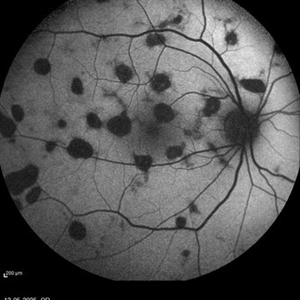

Healed Choroiditis

Auto fluorescence image of a 42 year old woman with healed choroiditic patches.

Photographer: Dr Moazzam Parvez, Netralayam, Kolkata

Imaging device: Heidelberg Spektrales

Condition/keywords: multifocal choroiditis